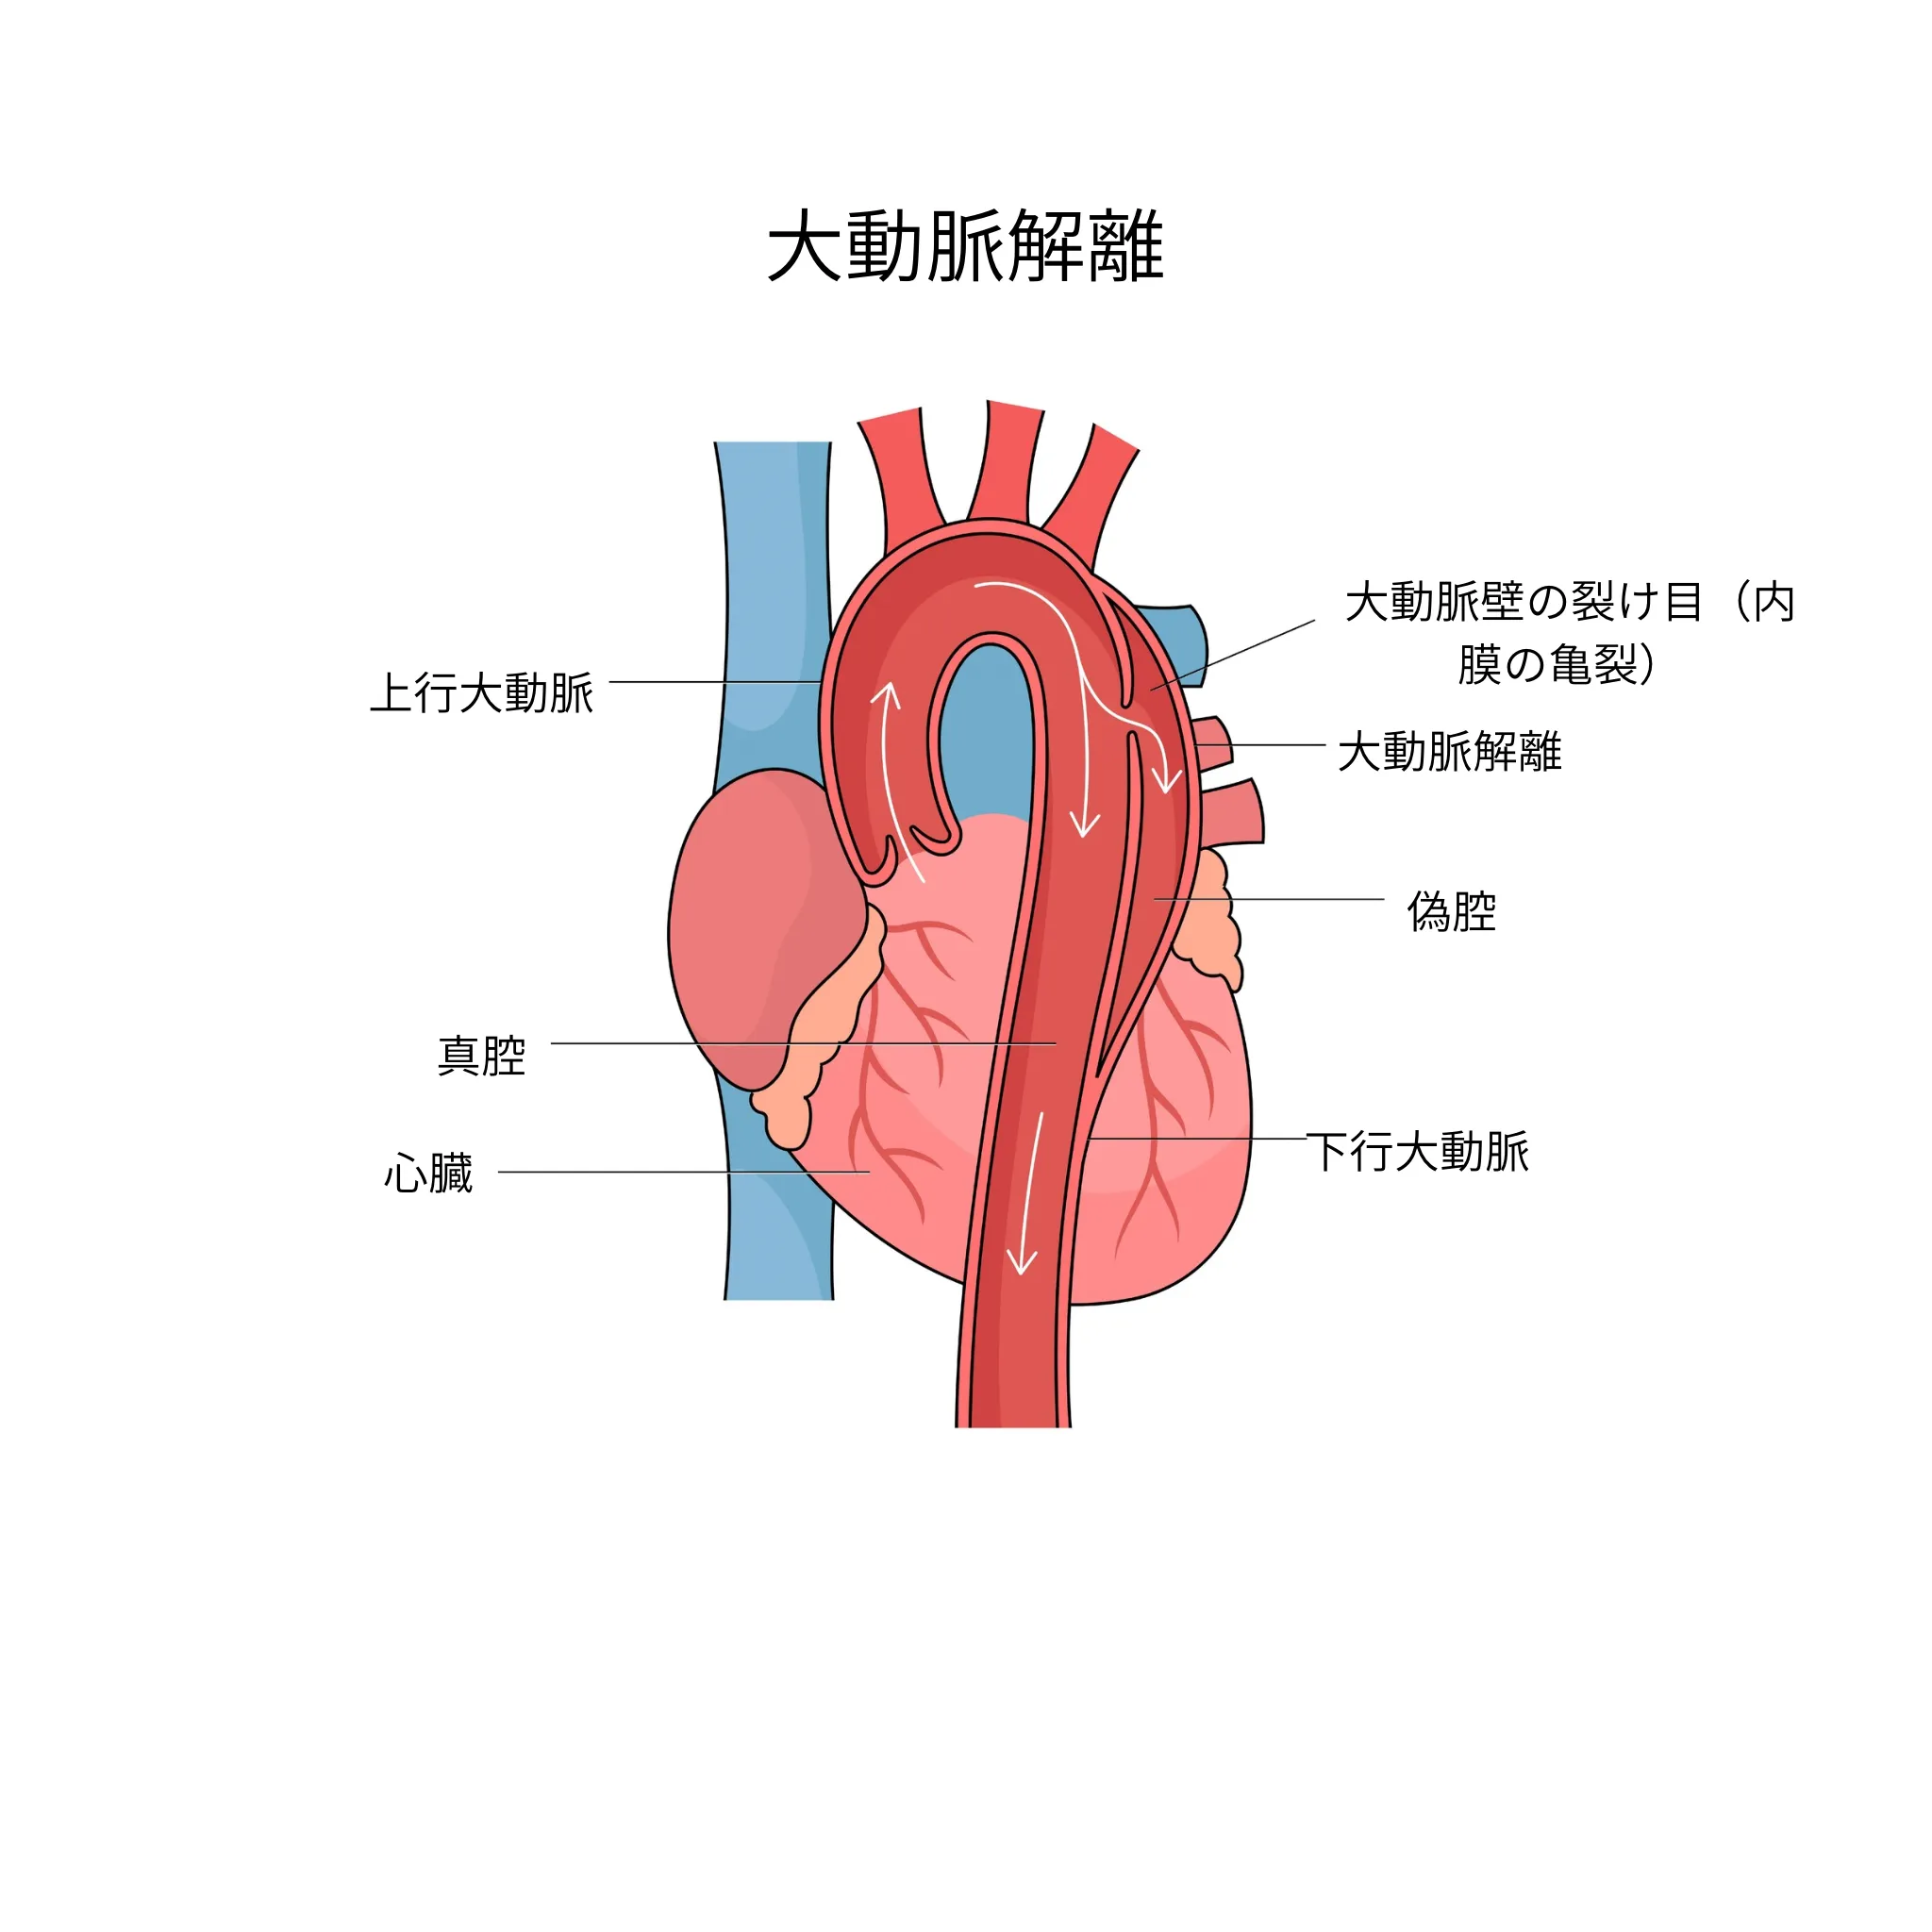

大動脈解離

大動脈解離は、大動脈の壁が裂ける病気で、突然の激しい胸痛や背中の痛みが特徴です。緊急の治療が必要な重篤な状態であり、速やかな対応が求められます。

大動脈解離では、突然の激しい胸痛や背中の痛みが特徴です。「裂けるような」「刺されるような」と表現される激痛で、痛みの場所が胸から背中、腹部へと移動することがあります。冷や汗や吐き気を伴い、意識を失うこともあります。この症状がある場合は、直ちに救急車を呼ぶ必要があります。

大動脈解離は緊急の治療が必要です。当院で大動脈解離が疑われる場合は、都立墨東病院をはじめとする連携医療機関へ速やかに紹介いたします。